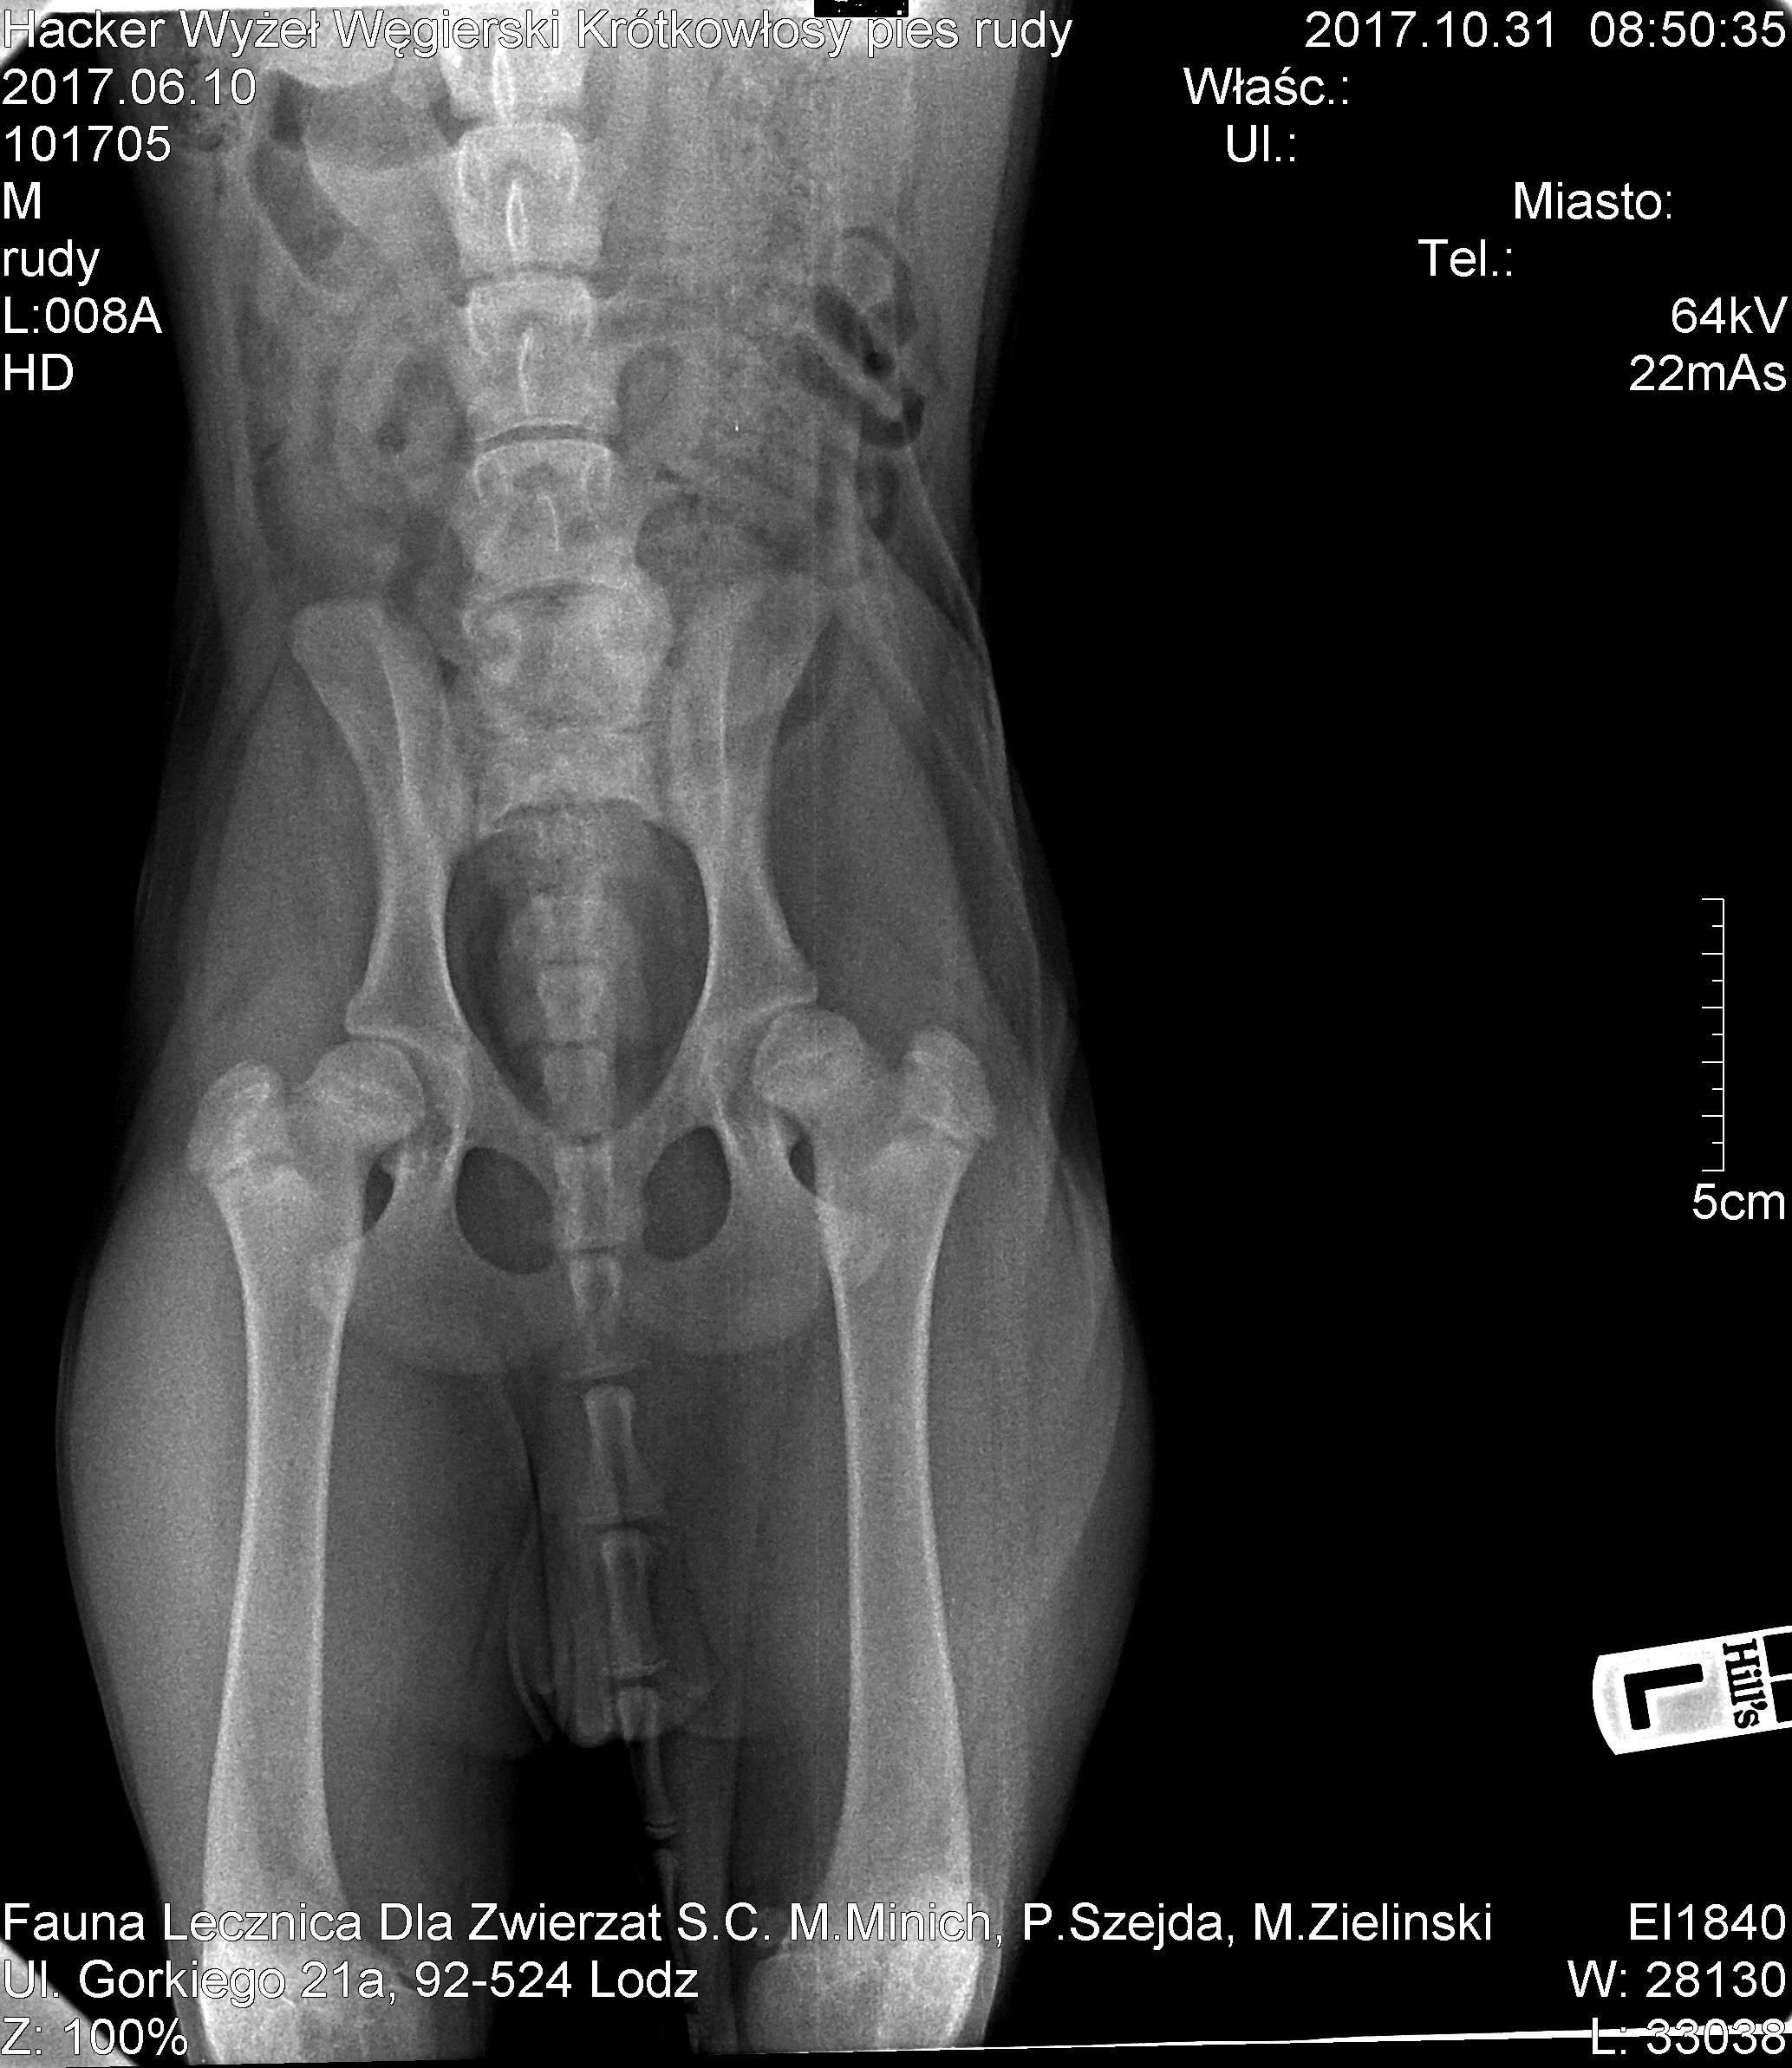

9. Hej, niestety musze napisac w tym watku posta, chociaz nigdy bym sie tego nei spodziewala kupujac psa z rodowodem (FCI) po zdrowych/ przebadanych rodzicach. Kilka dni temu ,moj psiak(20 tygodni) zaczal kulec na przednia prawa lape po spacerze i szalonych gonitwach z psami. Nie przeszlo na drugi dzien wiec zabralam psiaka do weta/ortopedy. Zbadal go namacalnie i powiedzial, ze pies ma bolace lokcie(ale zle nie jest i ze mu powinno przejsc bo pewnie to kwestia tego ze jedna kosc rosnie szybciej od drugiej i zrobily sie przerwy). Psiak dostal leki przeciwzaalne i przeciwbolowe, zalecenie zmiany karmy na adulta, podawanie supli Aniflexi (w naszym przypadku) i ograniczenie ruchu., Powiedzial, ze wedlug niego nei ma sensu robic rtg. Biodra bezbolesne totalnie. Nie dawalo mi to spokoju, bo jednak psiak od czasu do czasu kuśtyknie na ta prawa lapke, zauwazylam ze przez weekend nasilalo to sie po spacerze(na smyczy), jak juz odpoczal. Poszlam z nim jeszcze raz do lecz\nicy i powiedzialam, ze chce zrobic rtg... i dzis zostalo ono zrobione. Lokcie sa ok, tak jak lekarz mowil, chodzilo o kosci ktore rosna w roznym tempie i zrobily sie minimalne luzy, ktore maja zniknac, Bolesnosc jest wywolana przez krwiaczki, ktore sie tam zrobily. To mnie w miare ucieszylo, natomiast wetowi nie spodobaly sie biodra. Uznal ze wyglada na mocne HD-B wchodzace w C... Zasugerowal zabieg pectinectomii i podciecia spojenia łonowego. Powiedzial, ze to profilaktyka i ze spowolni postepujace zmiany o 70%. Ze jest szansa, ze to sie zatrzyma na tym etapie ale ze z reguly takie zmiany sie poglebiaja... Co robic? Zabieg? Planuje tez konsultacje z innymi polecanymi mi ortopedami, tylko ze wzgledu na zaawansowanie ciazy (8 miesiac) chce to zrobic stacjonarnie, czyli bez wyjazdow poza Lodz, gdzie mieszkam. Ps: gdyby ktos sie czepial ze zdjecie bioder jest krzywe, poprosilam weta o to zeby zrobil biodra pogladowo (bo problemu z nimi nie bylo), wiec wet robil to zdjecie sam przytrzymujac psa i wyszlo troszke krzywo ale zmiany widac wyraznie/. Poprosze o rady bo jestem w temacie zielona... Nie mam pojecia co robic :(